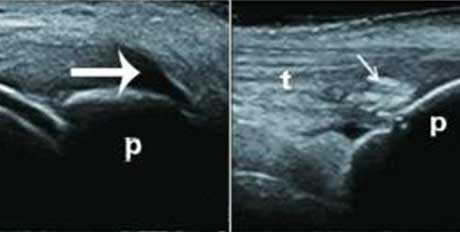

高回声带

软骨表面回声增强,与深面的骨性关节面强回声线形成“双轨征”。

聚集体

髁软骨的双轨征状,显示髌腱内部的聚集体